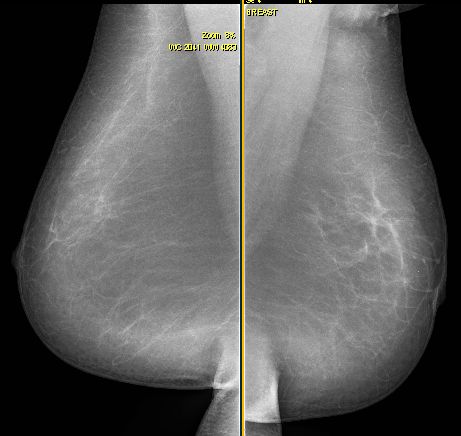

![]() ![]() 73 Jahre alte Frau. Vor 40 Jahren eitrige Mastitis puerperalis links oben außen. Jetzt 50mm großes invasives lobuläres Karzinom links oben außen. Tumor durch Mastitisnarbe maskiert. | ||